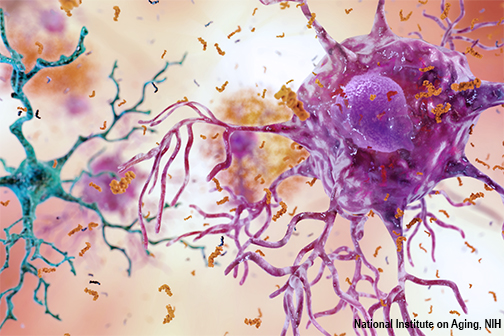

LSU Health New Orleans Discovers Major Contributor to Alzheimer’s Disease

Research led by Drs. Yuhai Zhao and Walter J Lukiw at the LSU Health New Orleans Neuroscience Center and the Departments of Cell Biology and Anatomy, Neurology and Ophthalmology, reports for the first time a pathway that begins in the gut and ends with a potent pro-inflammatory toxin in brain cells contributing to the development of Alzheimer’s disease (AD). They also report a simple way to prevent it. More

Study Reports Potential Target and Compounds to Slow the Development of Alzheimer’s Disease

Researchers at LSU Health New Orleans Neuroscience Center of Excellence and Karolinska Institutet have discovered a potential biomarker for Alzheimer’s disease diagnosis that may also serve as a therapeutic target. Examining cerebrospinal fluid samples from patients with cognitive impairment ranging from subjective impairment to a diagnosis of Alzheimer’s disease, they found a shift in the profile of specialized lipid mediators from pro-resolving to pro-inflammatory. The results of the exploratory study are published in the Springer journal, Cellular and Molecular Neurobiology. More

Study Shows That Intranasal Rx Halts Memory Decay in Experimental Alzheimer’s Model

A research collaboration between scientists at LSU Health New Orleans and the Karolinska Institutet in Sweden has found that applying specialized pro-resolving lipid mediators intranasally arrested memory loss and brain degeneration in an experimental model of Alzheimer’s Disease (AD). The results are published in the Nature journal, Communications Biology. More